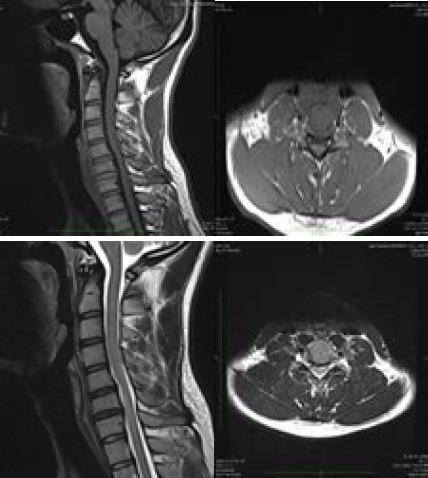

平山病是一种罕见的良性神经系统疾病,主要累及C5至T1脊髓前角,主要累及C7和C8。平山病是由于脊髓过度拉伸导致脊柱与硬脑膜之间生长不平衡,导致脊髓前部微循环紊乱,尤其是颈部屈曲时,引起单侧或很少不对称的双侧上肢无力和肌肉萎缩。这是一个21岁的男孩,他的左手和前臂虚弱了2年,在寒冷的天气和颈部弯曲时加重。颈部x线平片和颈椎MRI显示平山病的特征。

Hirayama disease is a rare benign neurological disease that affects the anterior horn of the spinal cord at C5 to T1, mainly at C7 and C8 due to imbalance growth between the vertebral column and the dura mater leading to microcirculatory disturbances in the anterior portion of the spinal cord due to overstretched cord, especially during flexion of the neck causing unilateral or rarely asymmetrically bilateral upper limb weakness and muscle wasting. It is a case of a 21-year-old boy presented with weaknesses in his left hand and forearm for 2 years which aggravates during cold weather and flexion of the neck. A plain x-ray of the neck and MRI of the cervical spine were conducted which show the features of Hirayama disease.